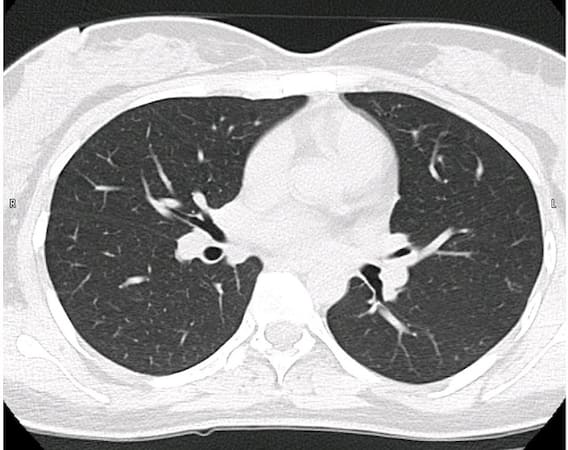

150 પરિવારોને પોતાના સ્વજનના મૃતદેહ આપવાની અપીલ બાદ 11 મૃતદેહ ફોરેન્સિક સાયન્સ વિભાગને મળ્ય હતા. પોસ્ટમોર્ટમ દરમિયાન સામે આવ્યું કે દર્દીના 400 ગ્રામના ફેફસા પથ્થર જેટલા કડક થઇ ગયા હતા અને તેનું વજન 3 થી 4 કિલોગ્રામ થઈ ગયું હતું. સાથે જ શરીરની અંદર આવેલી નસોમાં પણ લોહી જામી જવાની સ્થિતિ જોવા મળી હતી. જે અંગે સિવિલ હોસ્પિટલના ઓટોપ્સી વિભાગ દ્વારા રિપોર્ટ તૈયાર કરીને આગામી સમયમાં રાજ્ય સરકારને સોંપવામાં આવનાર છે.